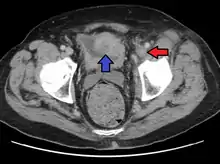

Deep vein thrombosis of the left external iliac in a person with bladder cancer resulting in this condition. (Author James Heilman, MD, 2016)